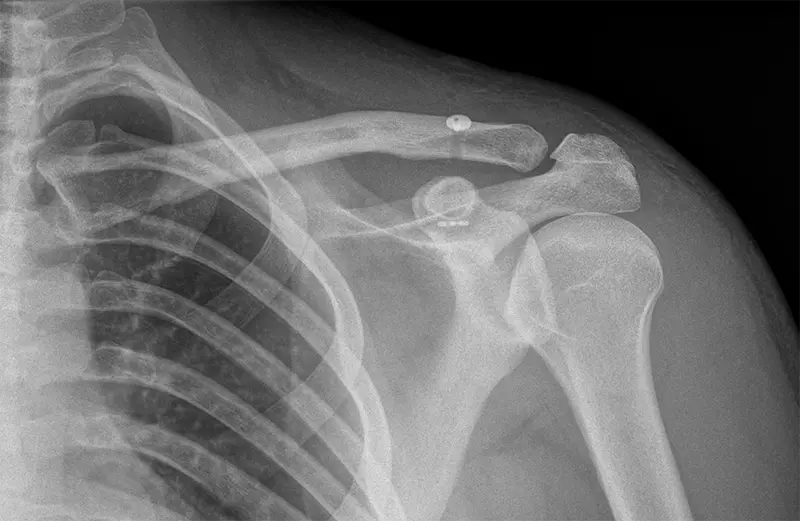

Rekonstrukcja więzadła barkowo-obojczykowego

Rekonstrukcja więzadła barkowo-obojczykowego to zabieg, który ma na celu zmniejszenie diastazy barkowo-obojczykowej. Procedura ta odgrywa kluczową rolę w zapobieganiu opadaniu kończyny górnej oraz zmniejszeniu przestrzeni barkowo-obojczykowej.

Diastaza barkowo-obojczykowa często jest wynikiem urazów, takich jak upadek na ramię. Procedura rekonstrukcji więzadła barkowo-obojczykowego może znacząco pomóc w redukcji diastazy i sprzyja gojeniu więzadeł w ciągu pierwszych 3 tygodni od urazu.